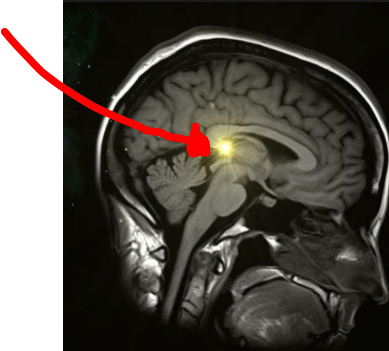

Pineal Gland Ct

Pineal gland ct. Original paper caries res 299135125 128 presented by permission of the author. Key words calcium distribution fluoride human pineal gland hydroxyapatite pineal. Pineal gland cyst symptoms. Loss of consciousness dizziness attacks of fear insecurity and loss of balance strange headaches tingling and pressure in my head.

A pineal cyst is a fluid filled mass that can occur in the pineal gland. True pineal gland cysts are not brain tumors. Rather they are a completely benign cyst. Melatonin is a hormone produced by the pineal gland among other locations which regulates wakefulness.

Advanced treatment of pineal cysts. Pineal cysts are benign fluid filled deposits located in the pineal gland region of the brain. Although most pineal cysts are. High prevalence of pineal cysts in healthy adults demonstrated by high resolution noncontrast brain mr imaging.